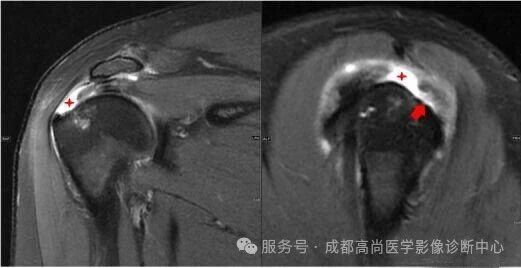

右肩 MRI 检查图像

图 1—5 MRI 平扫示右肩冈上肌肌腱失去正常形态结构,局部显示欠连续,肌腱附着点未见正常结构显示,提示冈上肌腱断裂。